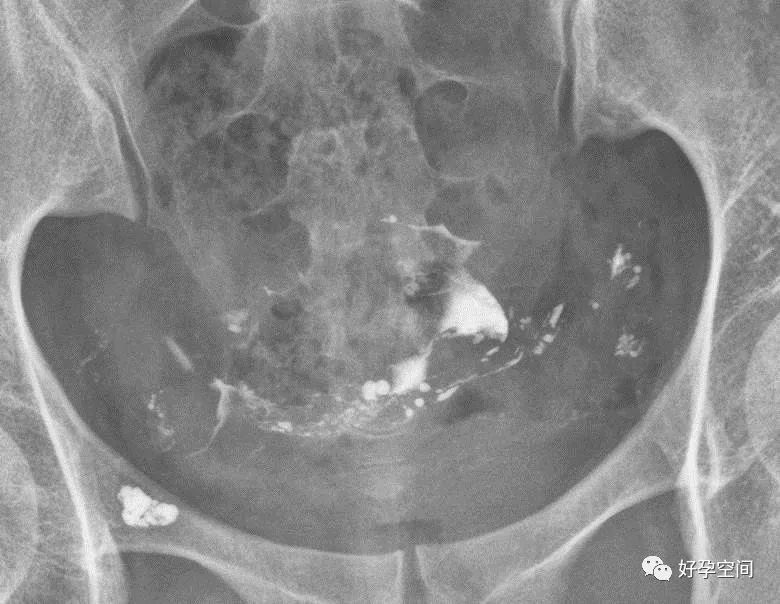

6、子宫肌瘤钙化

盆腔内见类圆形蛋壳样高密度影

7、畸胎瘤钙化

盆腔内见牙齿状高密度钙化影